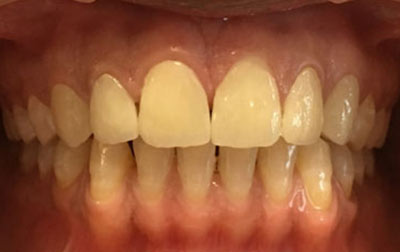

Smile makeover:

Radiating confidence through a beaming smile can truly uplift your spirits. A captivating smile holds significant sway in social and professional spheres, enhancing your overall appeal. However, numerous individuals refrain from revealing their teeth in public or photographs due to personal dissatisfaction. If you find yourself in this category, why not consider allowing us to assist you in attaining the smile you've always envisioned? Embark on a journey toward your ideal smile with our transformative smile makeover. A smile makeover transcends the mere resolution of dental issues as they arise. It constitutes a holistic plan to rejuvenate your smile, intricately tailored to complement your distinct facial features and aesthetic inclinations. The outcomes are nothing short of remarkable—both in terms of your visual transformation and the surge of newfound confidence you'll experience.